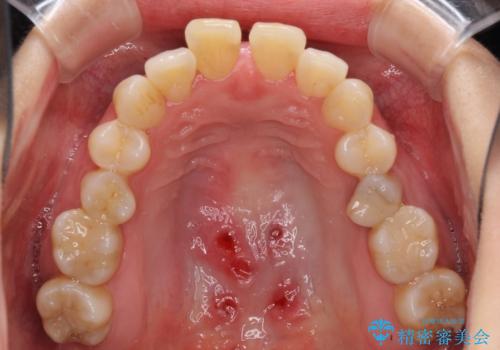

- 奥歯の咬み合わせを気にして来院された患者様です。

上顎骨の幅が下顎骨よりも小さいので、拡大装置により骨幅を広げて上下関係を改善し、その後インビザラインにて歯並びを整えることとしました。

上下の骨幅を改善したことで、スムーズに歯列矯正を行うことができました。

奥歯の咬み合わせを改善する必要があったため、治療は長期化しましたが、きっちりと仕上げることができました。